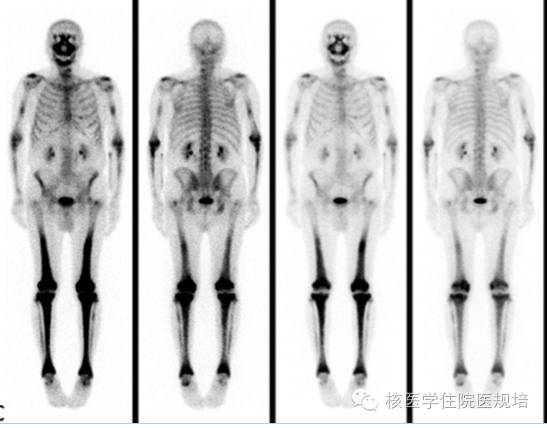

骨骼受累者约占96%,多为四肢长骨骨干、干骺端对称的成骨性骨质破坏,其中约一半患者可出现骨痛。X线及CT可表现为四肢长骨(下肢为主)骨干、干骺端双侧对称的弥漫性骨质硬化及骨膜炎(如图9),也可表现为溶骨性、混合性骨质破坏及中轴骨病变。ECD的全身骨显像可见四肢骨干、干骺端双侧对称性放射浓聚(如图10)。骨骼病的典型特征对疾病诊断有重要意义。

2、代谢性骨病:甲旁亢性代谢性骨病、肺性肥大性骨关节病、Paget病等代谢性骨病都可表现为四肢长骨皮质的放射性浓聚影,但各自有其影像特征,如甲旁亢骨病可见典型“黑颅征”、“领带征”“串珠肋”等,Paget病骨显像多见非对称的局灶放射性浓聚,可有骨骼变形,X线常见骨皮质增厚硬化等特征。而ECD骨显像中的典型表现为四肢长骨自关节端向骨干延伸的对称放射性浓聚,其在病变分布上与前三者有区别。而更重要的是,上述代谢性骨病临床上多有具提示意义的病史或实验室检查,且无多系统受累表现,因此,结合临床资料诊断并不困难。

ECD虽为罕见疾病,但影像表现具有特征性,认识该疾病的临床及影像表现可帮助临床早期诊断。由于骨骼为ECD的主要受累器官,全身骨显像对其诊断有重要提示作用。18F-FDG PET/CT可发现全身多系统的病变,并指导组织病理学检查部位的选取。![]() 图9. ECD患者的四肢骨X光片

图9. ECD患者的四肢骨X光片![]() 图10. ECD患者的全身骨显像

图10. ECD患者的全身骨显像![]() 图11. 右房假瘤样病变